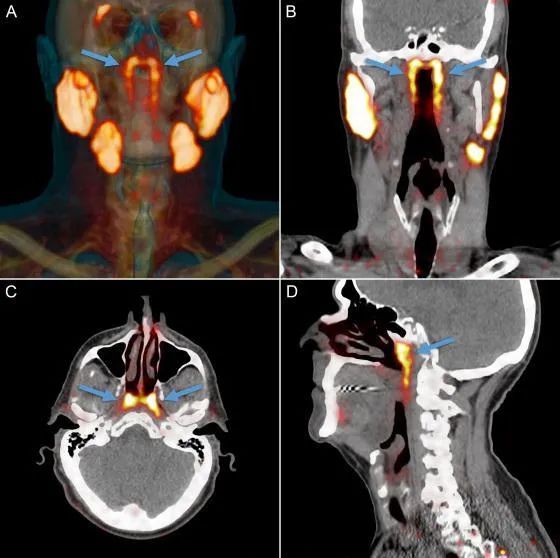

這種利用示蹤劑成像診斷癌症的方法被稱為**“PSMA PET-CT”**。

通過PSMA PET-CT,科學家們發現了第四種唾液腺

巧的是,PSMA PET-CT掃描也非常擅於發現唾液腺組織,因此在掃描成像的過程中就標記出了人體中所有唾液腺的位置,也意外地發現了新的唾液腺,這對扁平、細長的唾液腺位於鼻子到咽喉的深處,不顯眼地掛在連接耳朵和喉嚨的管狀結構上。